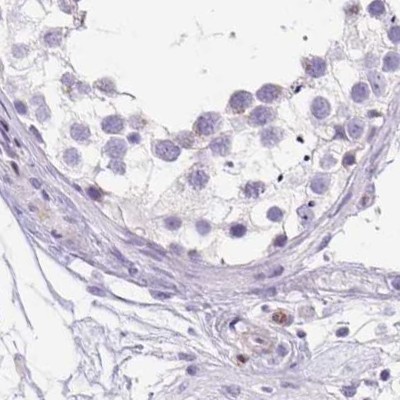

Immunohistochemistry analysis in human pancreas and colon tissues using Anti-ERP27 antibody. Corresponding ERP27 RNA-seq data are presented for the same tissues.